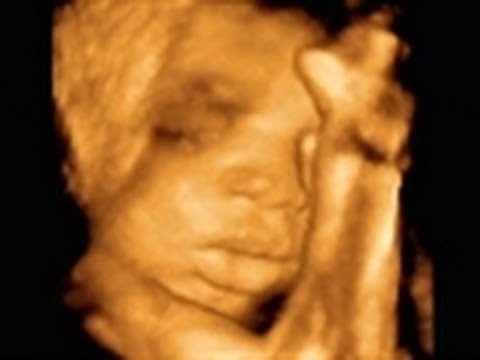

A lot of pregnant women worry about what kinds of sounds their unborn baby can hear. Some worry that classical music might be too jarring for the baby. We asked an expert if it was safe to listen to classical music while pregnant.